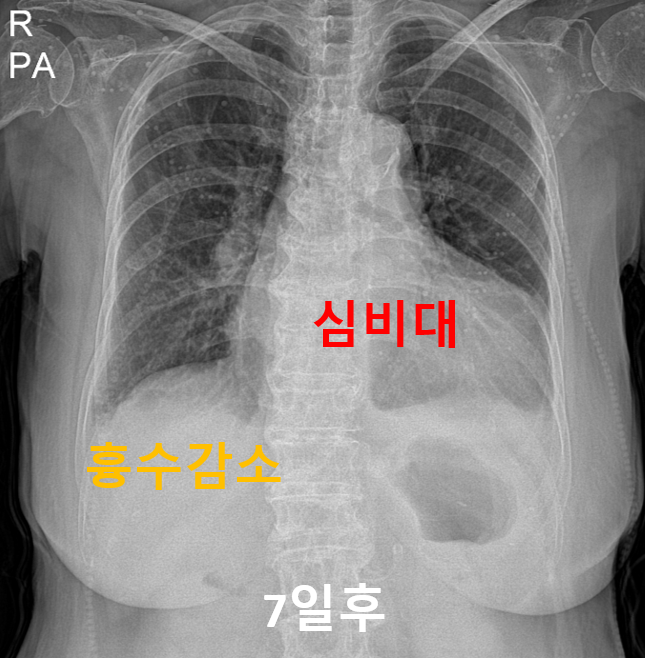

일주일후 엑스레이를 재시행하였더니 양쪽 흉수는 많이 줄어든 상태였으나 심장은 여전히 부어있었습니다.

그리고 또 열흘후 다시 엑스레이를 찍어보았더니 흉수는 완천히 사라지고 심장의 크기도 줄어든 상태였습니다.

특별히 입원 치료하지않고도 먹는 약제로 잘 조절하면서 증상호전되어 현재 잘 지내고 계십니다.